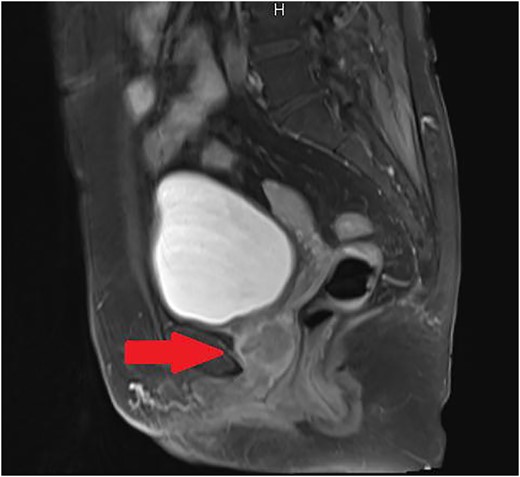

A 61-year-old woman presented to the gynecology department with complaints of atypical genital bleeding. Vaginal examination revealed an elastic-hard mass beneath the anterior vaginal wall. Magnetic resonance imaging (MRI) revealed a localized urethral tumor extended to vagina (Fig. 1). Histological test of the biopsy tissue of the mass suggested the adenocarcinoma. Computed tomography did not reveal any evidence of metastasis. Under the diagnosis of urethral tumor, the patient was referred to our department. Because the fenestration of the anterior vaginal wall was performed under the diagnosis of the abscess in the pelvic floor for the patient ∼15 years ago and the histological test demonstrates the adenocarcinoma, we suspected a urethral diverticular adenocarcinoma.

Sagittal T2-weighted MRI of the pelvis revealed a localized urethral tumor extended to vagina.